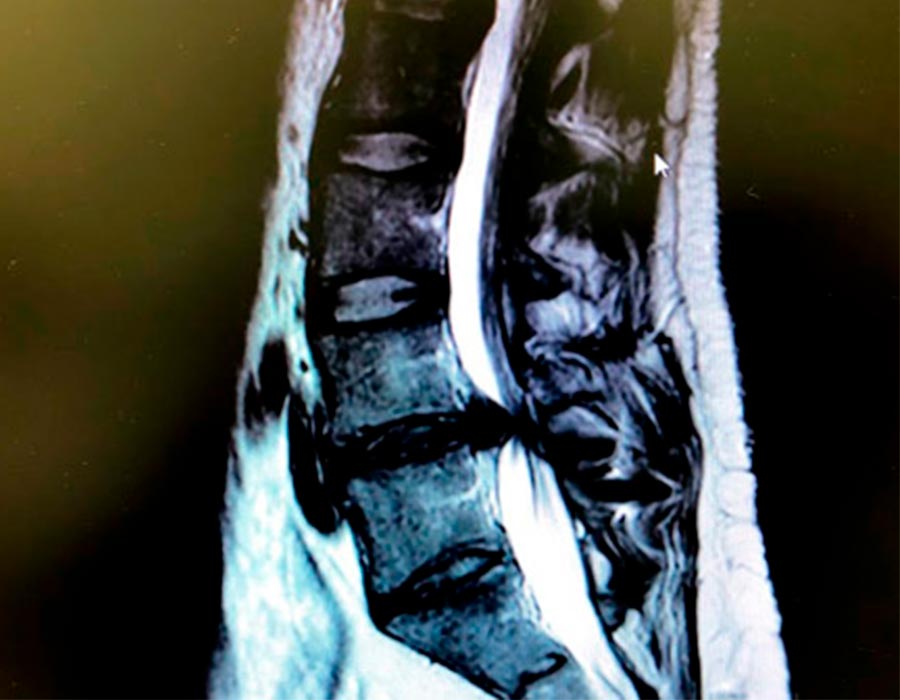

En el caso que os presentamos hoy nos encontramos con un paciente que, de una cirugía anterior, presenta una fijación en la quinta vértebra lumbar con el Sacro.

Preoperatorio

Esta artrodesis le ha provocado una nueva hernia discal lumbar en el nivel que hay por encima debido a la movilidad propia de este segmento. Esta nueva hernia le provoca una compresión en el canal medular y en los nervios que contiene.

Hernia discal lumbar a extraer